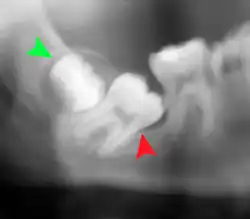

Impacted wisdom teeth are classified by the direction and depth of impaction, the amount of available space for tooth eruption, and the amount of soft tissue or bone (or both) that covers them. The classification structure helps clinicians estimate the risks for impaction, infections and complications associated with wisdom teeth removal.[6] Wisdom teeth are also classified by the presence (or absence) of symptoms and disease.[7]

Impacted wisdom teeth are often described by the direction of their impaction (forward tilting, or mesioangular being the most common), the depth of impaction and the age of the patient as well as other factors such as pre-existing infection or the presence of pathology (cysts, tumors or other disease).[5]: 143–144 Each of these factors is used to predict the difficulty (and rate of complications) when removing an impacted tooth, with age being the most reliable predictor[8] rather than the orientation of the impaction.[9]

Another classification system often taught in U.S. dental schools is known as Pell and Gregory Classification. This system includes a horizontal and vertical component to classify the location of third molars (predominately applicable to lower third molars): the third molar's relationship to the level of the teeth already in the mouth, being the vertical or x-component and to the anterior border of the ramus being the horizontal or y-component.[10]

Coronectomy

Coronectomy is a procedure where the crown of the impacted wisdom tooth is removed, but the roots are intentionally left in place. It is indicated when there is no disease of the dental pulp or infection around the crown of the tooth, and there is a high risk of inferior alveolar nerve injury.[32]